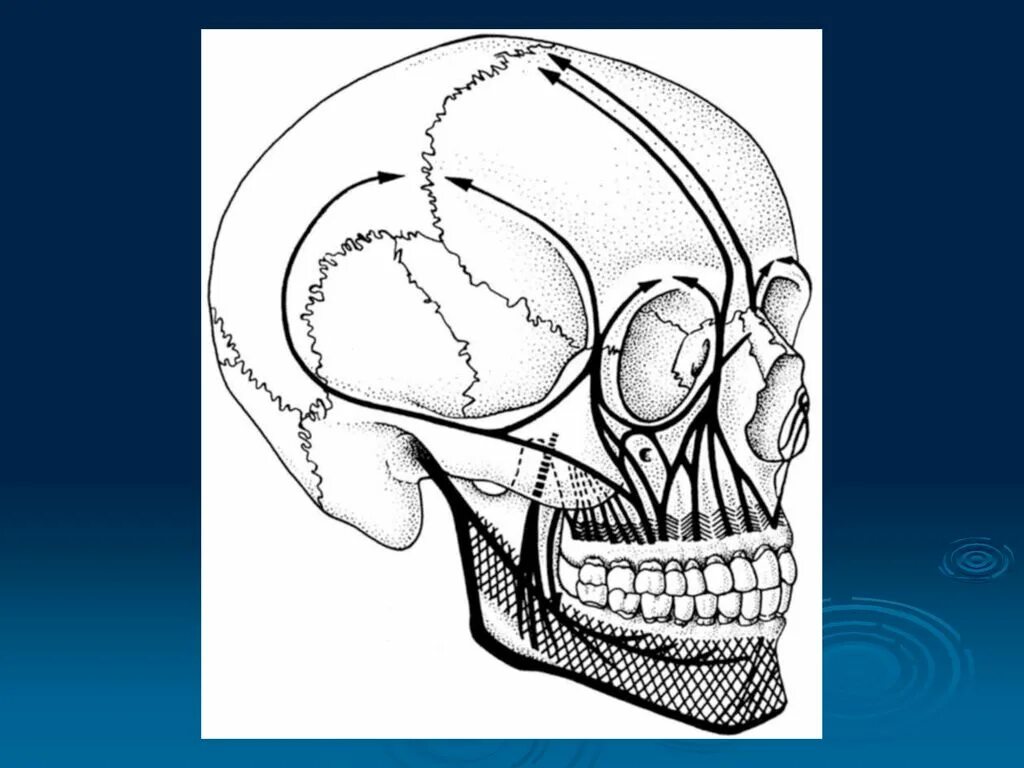

Остеопатия череп